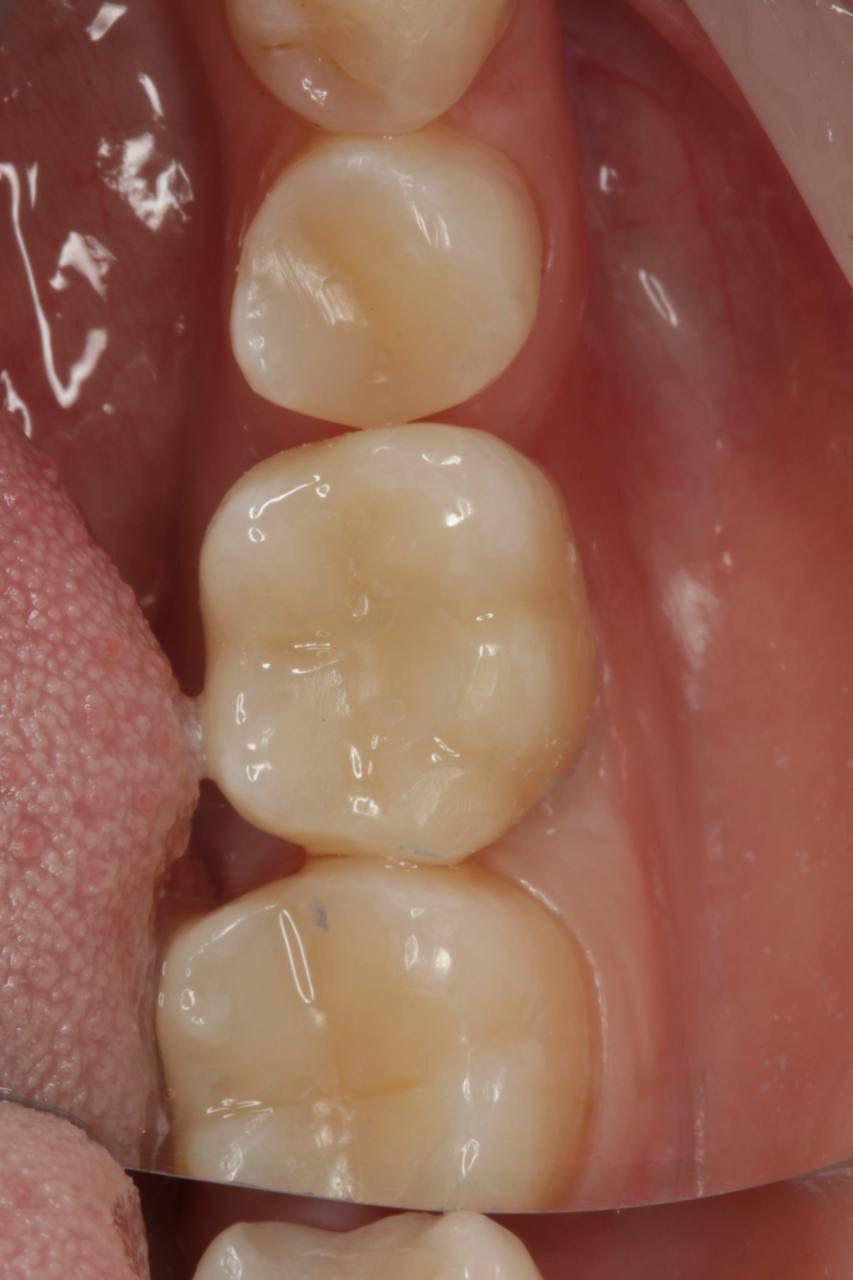

Одномоментная имплантация системой Osstem(Ю. Корея), подшит трансплантат с бугра(для увеличения объема мягких тканей), установлен формирователь десны. Через 3 месяца установлена коронка из диоксида циркония на винтовой фиксации